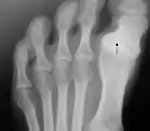

Anatómicamente forma parte de una cadena osteo-articular de tres piezas que prolonga el arco medial del pie partiendo de la primera cuña, el llamado «primer radio plantar». Sus componentes óseos parten del primer metatarsiano, y cuenta con solo dos falanges—siendo la falange media o segunda falange la que está ausente—[13] unidas mediante una articulación en pivote o trocoide, en tanto que el resto de dedos cuentan con tres. En la conexión metatarsiano-falange se encuentra el sistema glenosesamoideo, del que no disponen el resto de los dedos, y que está formado por dos huesos sesamoideos, que actúan a modo de polea (mecanismo sesamoideo) ayudando a los tendones de los músculos del dedo gordo en su función.[14] El sistema está formado por el cartílago glenoideo, que amplía la cavidad articular de la falange, y los dos huesos sesamoideos unidos por el ligamento intersesamoideo.[15]

También encontramos el ligamento de Lisfranc entre la base de la primera cuña y la cara interna de la base del segundo metatarsiano. Todos los dedos del pie poseen ligamentos intermetatarsianos que unen sus bases, salvo el dedo gordo con el segundo, el cual solo está unido a la cuña. Esto permite individualizar los desplazamientos, que en el resto de los dedos suceden en bloque debido a los ligamentos intermetatarsianos.[16]